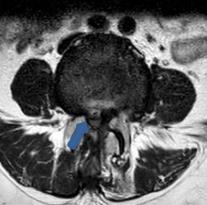

• 脊柱内镜侧后路联合减压术治疗腰神经根双卡综合征的临床疗效观察

2025, 31(12):25-32. DOI: 10.12235/E20250012

摘要 (122) HTML (46) PDF 10.14 M (90) 评论 (0) 收藏

摘要:目的 观察脊柱内镜侧后路联合减压术治疗腰神经根双卡综合征(DCS)的临床疗效、可行性、安全性和有效性。方法 回顾性分析2018年9月-2023年9月于该院就诊的50例腰椎退行性病变致腰神经根DCS患者的临床资料,根据手术方法不同,将患者分为观察组(37例)和对照组(13例)。观察组行脊柱内镜侧后路联合减压术治疗,对照组行非手术治疗。比较两组患者治疗前、治疗后1周、治疗后3个月、治疗后6个月和治疗后12个月的疼痛视觉模拟评分法(VAS)评分、Oswestry功能障碍指数(ODI)和日本骨科协会(JOA)评分。末次随访时,采用改良Macnab标准,评估临床疗效;采用腰椎MRI检查,评估椎间隙高度和椎间盘退变改良Pfirrmann分级。比较两组患者治疗的安全性(包括:并发症发生情况、复发情况和转手术治疗情况)。结果 50例患者均顺利完成治疗。两组患者术后VAS评分和ODI呈下降趋势,JOA评分呈升高趋势,观察组术后各时点VAS评分和ODI明显低于术前,且明显低于对照组,术后各时点JOA评分明显高于术前,且明显高于对照组,差异均有统计学意义(P < 0.05);观察组优良率为86.49%,明显高于对照组的76.92%,差异有统计学意义(P < 0.05);两组患者末次随访时,椎间隙高度和椎间盘退变Pfirrmann分级比较,差异均无统计学意义(P > 0.05)。两组患者围手术期均未出现神经损伤和脑脊液漏等严重并发症,观察组术后1例出现下肢放射性疼痛;观察组1例术后3个月出现腰椎间盘再突出;对照组有3例转手术治疗。结论 与非手术治疗相比,脊柱内镜侧后路联合减压术可更为安全、有效地缓解腰神经根DCS患者的疼痛,改善下肢功能,且早、中期临床疗效好。值得临床推广应用。